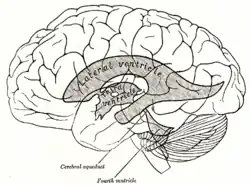

Срединный сагиттальный срез головного мозга. Желудочки головного мозга, вид сбоку.

Желудочки головного мозга, вид сбоку.